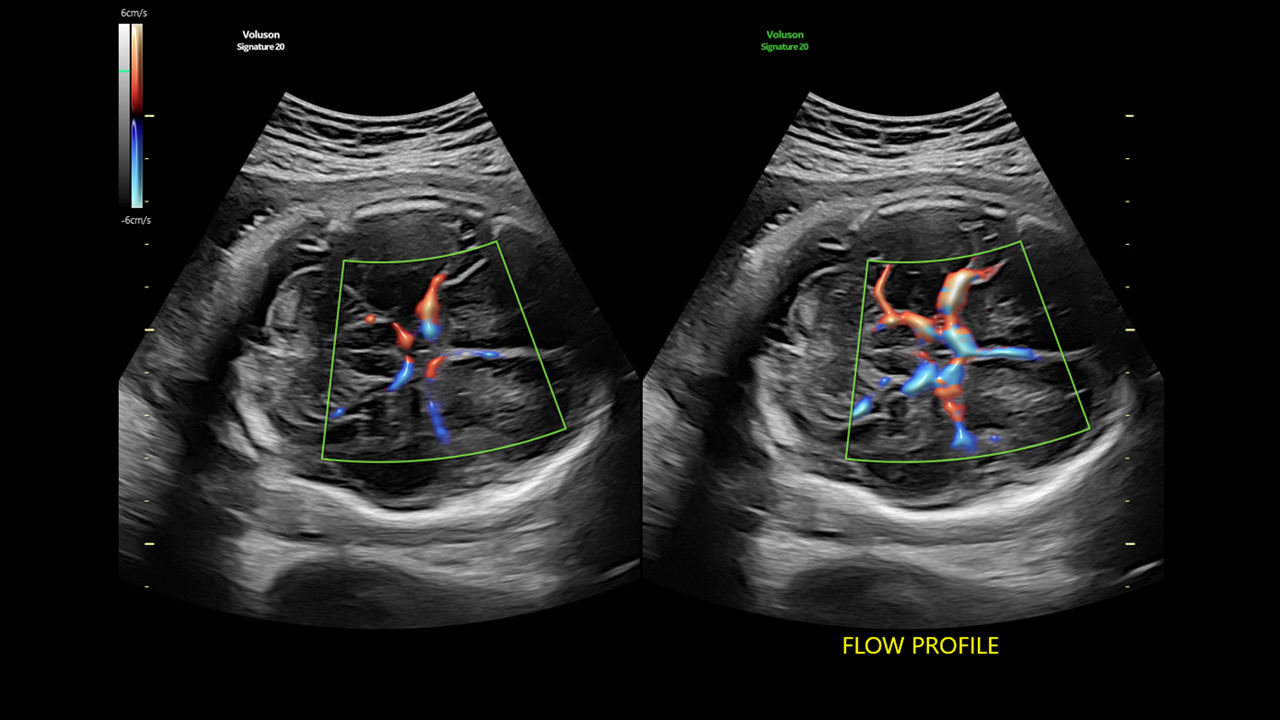

Flow Profiles

Reduce exam time by 56% with Flow Profiles. Dramatically simplifies color and pulsed-wave Doppler optimization by utilizing predefined and optimized settings.